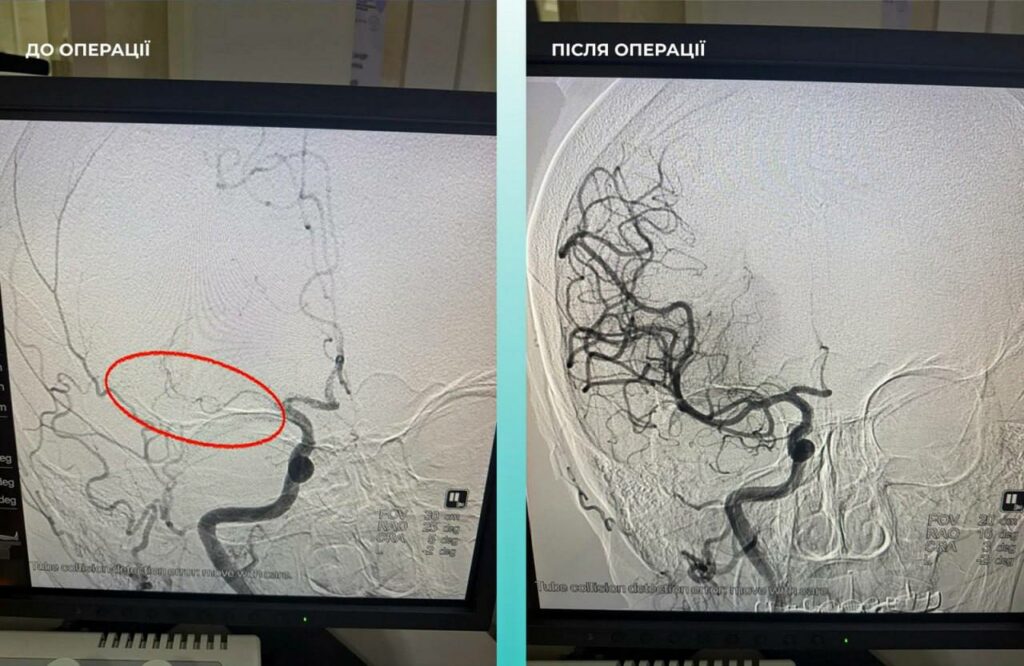

Пацієнтка потрапила до лікарні з ознаками важкого інсульту. Комп’ютерна томографія підтвердила закупорку середньої мозкової артерії. Однак лікарі помітили, що жінці важко дихати. Додаткове обстеження виявило ще одну смертельну небезпеку — тромбоемболію легеневої артерії.

Мультидисциплінарна команда лікарів пішла на ризик і прийняла життєво необхідне рішення: провести тромбектомію (видалення тромбів) одночасно на двох критичних ділянках — у мозку та легенях.

Завдяки професіоналізму медиків операція пройшла успішно. Наразі стан жінки значно покращився, вона перебуває під наглядом фахівців.